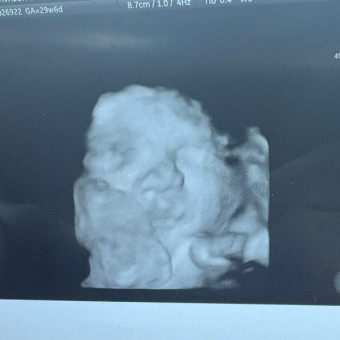

Baby Sister 🩷

Avalon Beck & Ryker Beck

Hurricane, UT

November 27, 2025